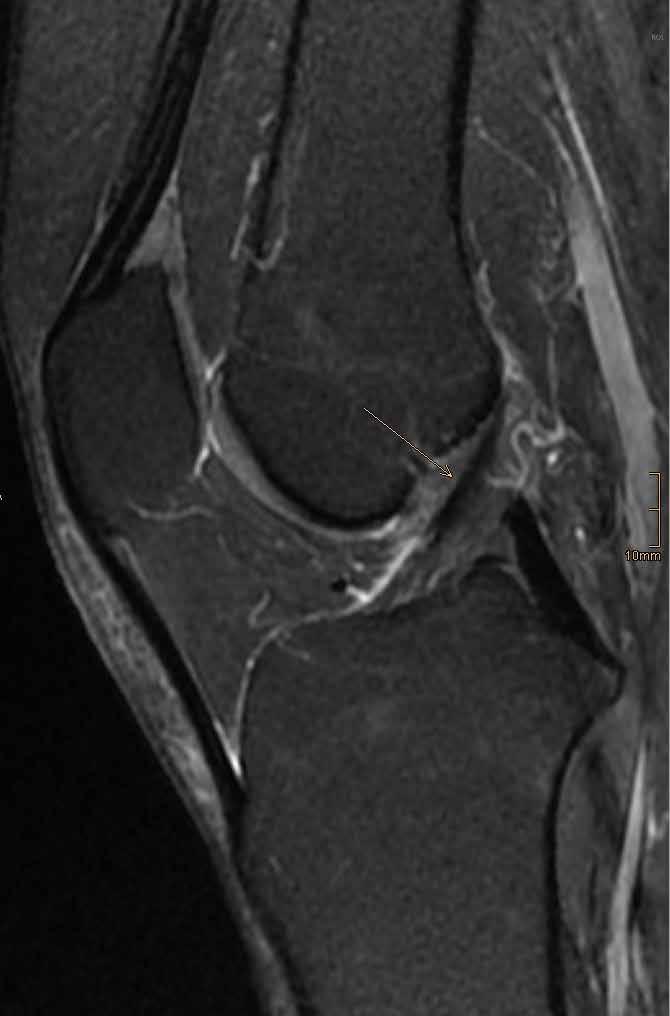

Der Blick ins Knie

Wenn es bei Bewegung schmerzt oder zwickt, ist eine exakte Diagnose entscheidend. Da kommen auch die Radiologen ins Spiel: PD Dr. Thorsten Klink, Direktor des Instituts für diagnostische und interventionelle Radiologie an der Klinikum Bayreuth GmbH, macht einen Blick ins Knie möglich. Hier wird deutlich, was moderne Bildgebung kann. KREUZBANDRISS

KLINIKUM BAYREUTH GMBH > RADIOLOGIE O B E R S C H E N K E LK N O C H E N S C H I E N B E I NK N O C H E N GELENKERGUSS K N I E S C H E I B E K N I E S C H E I B E Kreuzband-

VORDERES KR E U Z B A N D HINTERES KREUZBAND

Riss Normales Kreuzband

KreuzbandPlastik

35 S C H I E N B E I NK N O C H E N S C H I E N B E I NK N O C H E N O B E R S C H E N K E LK N O C H E N O B E R S C H E N K E LK N O C H E N K N I E S C H E I B E S C H RAU B E KREUZBANDPLASTIK

H I N TERES KREUZB A N D